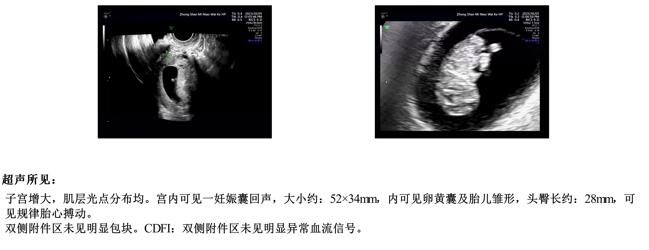

检查中发现宫腔异常,宫腔镜下行子内膜息肉切除,发现子宫内膜炎予以抗炎治疗后复查内膜CD138阴性。同步免疫治疗,2023年8月自然周期移植1枚囊胚,顺利接到好孕,顺利“毕业”!